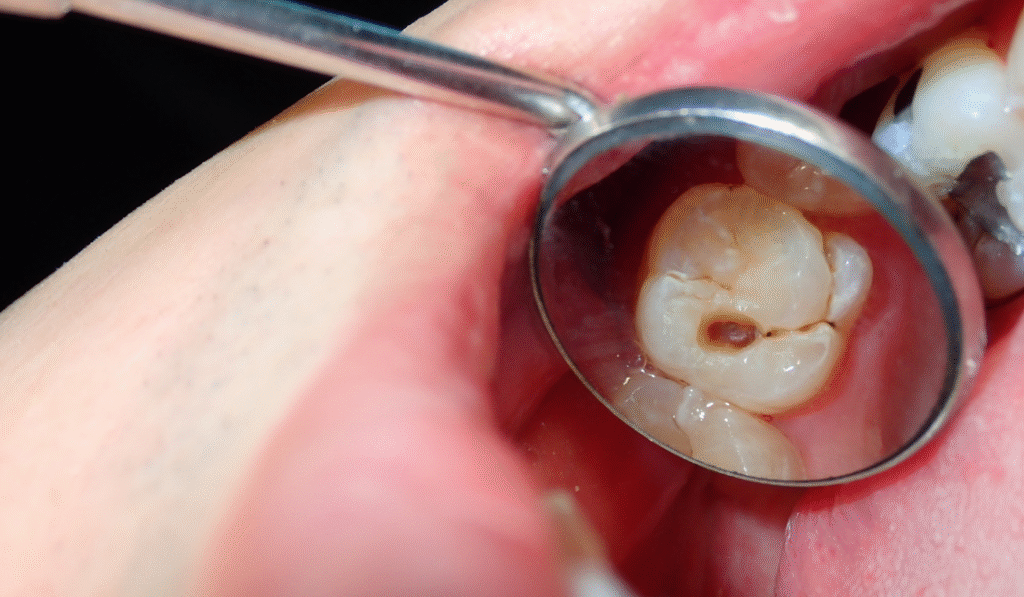

• Las caries también son un problema frecuente en las muelas del juicio, ya que su ubicación las hace menos accesibles para el cepillado. Si no se tratan a tiempo, estas caries pueden desencadenar un dolor severo y complicaciones más graves.

Un empaste dental es un tratamiento crucial en odontología que tiene como objetivo reparar un diente afectado por caries. La caries, resultado de la acción de ácidos producidos por las bacterias que se alimentan de los restos de alimentos, puede comprometer la salud dental si no se interviene a tiempo. Cuando el daño ha sido identificado, es fundamental realizar un empaste para restaurar tanto la funcionalidad como la estética del diente.

La función principal del empaste es eliminar el tejido dañado por la caries y rellenar la cavidad resultante con un material especial que devuelva al diente su forma y resistencia. Este procedimiento ayuda a prevenir que la caries avance y cause problemas más serios, como infecciones o la necesidad de tratamientos más invasivos.

• Aparición de manchas oscuras o claras en el diente.

El uso de tecnología avanzada, como radiografías, complementa la evaluación visual, permitiendo detectar caries en etapas tempranas antes de que se conviertan en problemas mayores. Estas imágenes son valiosas para entender la magnitud del daño y planificar el tratamiento apropiado.